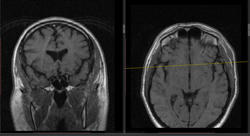

- https://radiomed.ru/sites/default/files/styles/case_slider_image/public/user/16807/7_5.jpg?itok=rB786yvP

- https://radiomed.ru/sites/default/files/styles/case_slider_image/public/user/16807/9_2.jpg?itok=dLUwi9M9

дифференциальная диагностика ganglion ,нодулярный фасциит,нейрофиброма,дерматофиброма